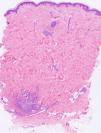

Punch biopsies and microscopic examination revealed similar features in the 3 cases. The epidermis was essentially normal. There was a dense perivascular and periductal infiltrate of neutrophils in the dermis with duct infiltration. In the eccrine glands, there was vacuolar degeneration and necrosis of the epithelial cells, predominantly in the secretory portion. Microabscess formation was also seen in this portion (Figs. 2 and 3). Vascular damage adjacent to neutrophilic abscesses was identified in patients 1 and 2. Ziehl-Neelsen and Gram staining revealed branching, beaded, filamentous, gram-positive bacteria with morphologic features of Nocardia species in patient 1 and gram-positive cocci in the lumen of the eccrine sweat gland coil in patient 3. In addition, tissue culture confirmed the presence of Nocardia species in patient 1, M. chelonae in patient 2, and S. aureus in patient 3.

In addition to the characteristic histological features reported in the literature, in our 3 cases we also saw considerable vascular damage, adjacent to neutrophilic abscesses in patients 1 and 2.